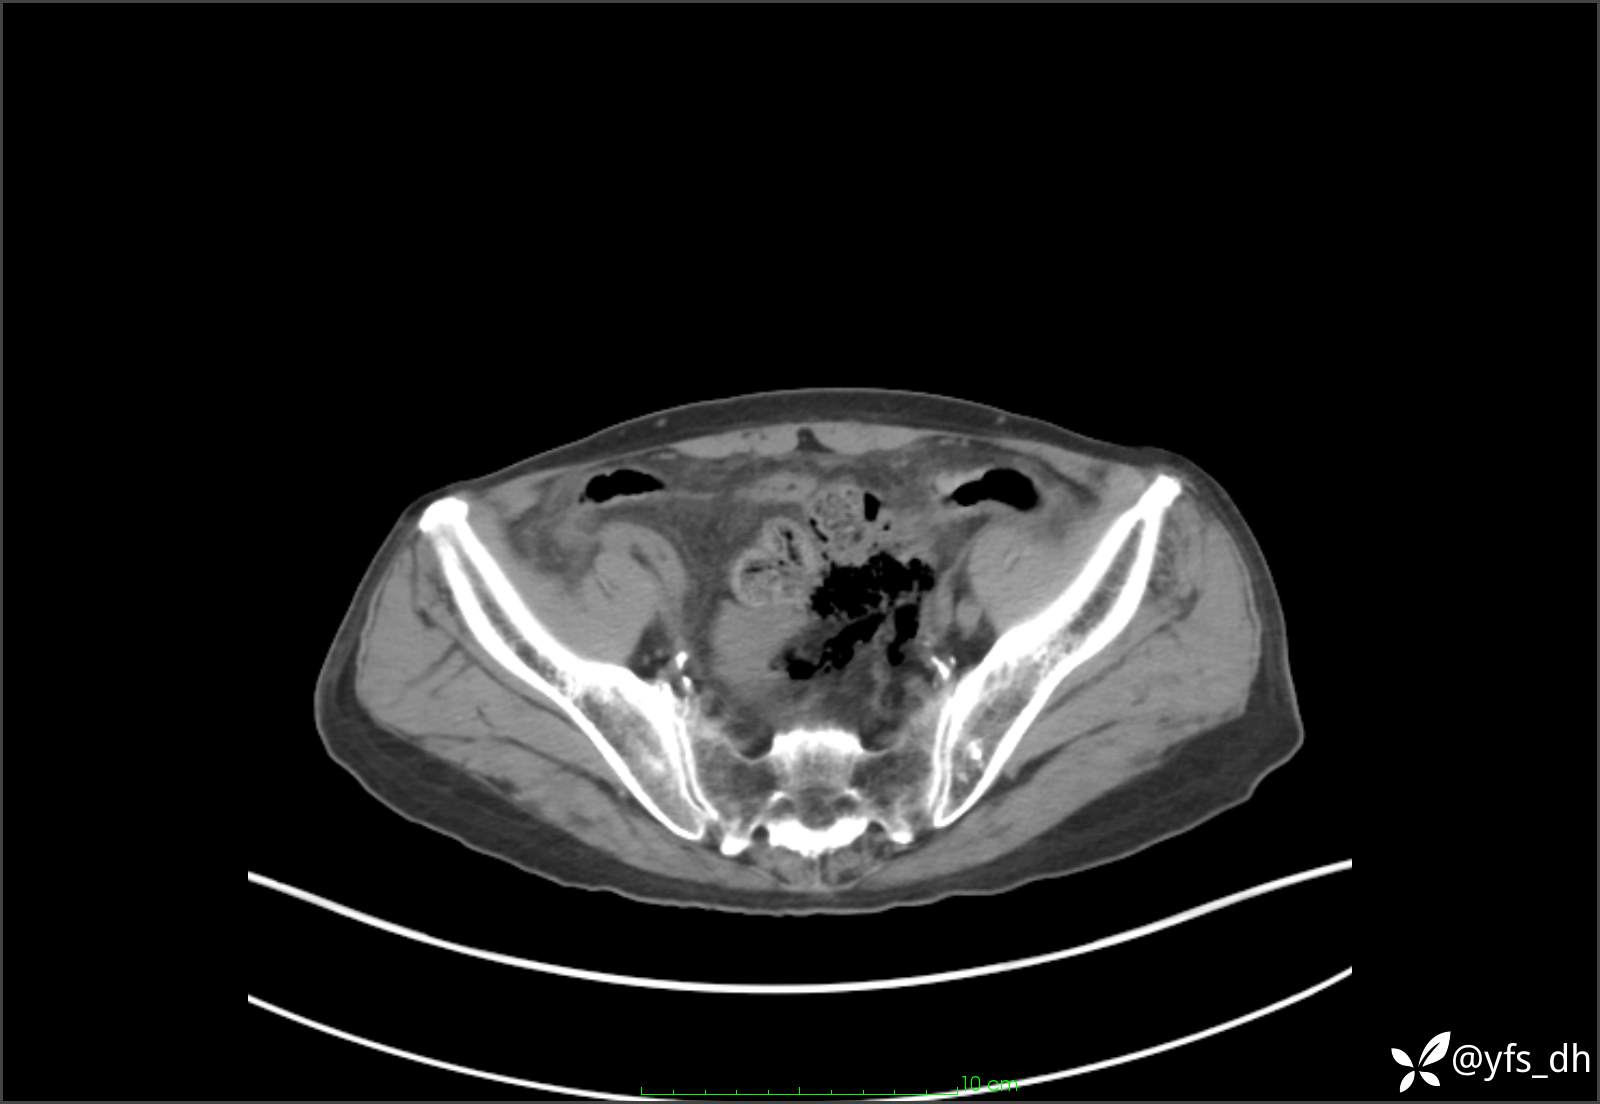

1.简要病史:患者4天前突发上腹部疼痛不适,但可以忍受。3小时前饭后突然加重,不能忍受后就诊。

2.简要手术记录:术中见腹盆腔大量肠液及粪便,乙状结肠中下段见一约3cm的破口。